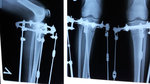

Дата операции 03.12.2015г.

Дата снятия аппаратов 09.03.2016г.

Срок лечения 95 дней.